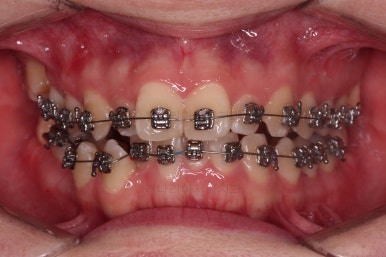

부산교정치과 초진 시 입안의 모습입니다.

앞니가 삐뚤어서 결손치아가 없었더라도 교정치료를 원하셨던 상황이었고요.

오른쪽 어금니 맞물림은 결손치아도 그렇지만 전반적인 앞뒤 차이가 있는 부정교합이 있었어요.